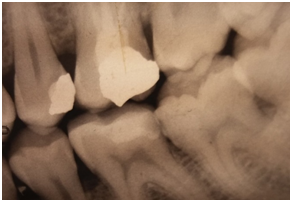

The vitality test revealed a positive response of the 46. The radiological examination showed a large-scale amalgam restoration at a distance from the pulp (Figure 2). After clinical examination, the appropriate treatment option was a ceramic onlay restoring the 46 using the IPS e.max CAD system.

Figure 2 Periapical radio on the 46: a large-scale amalgam.